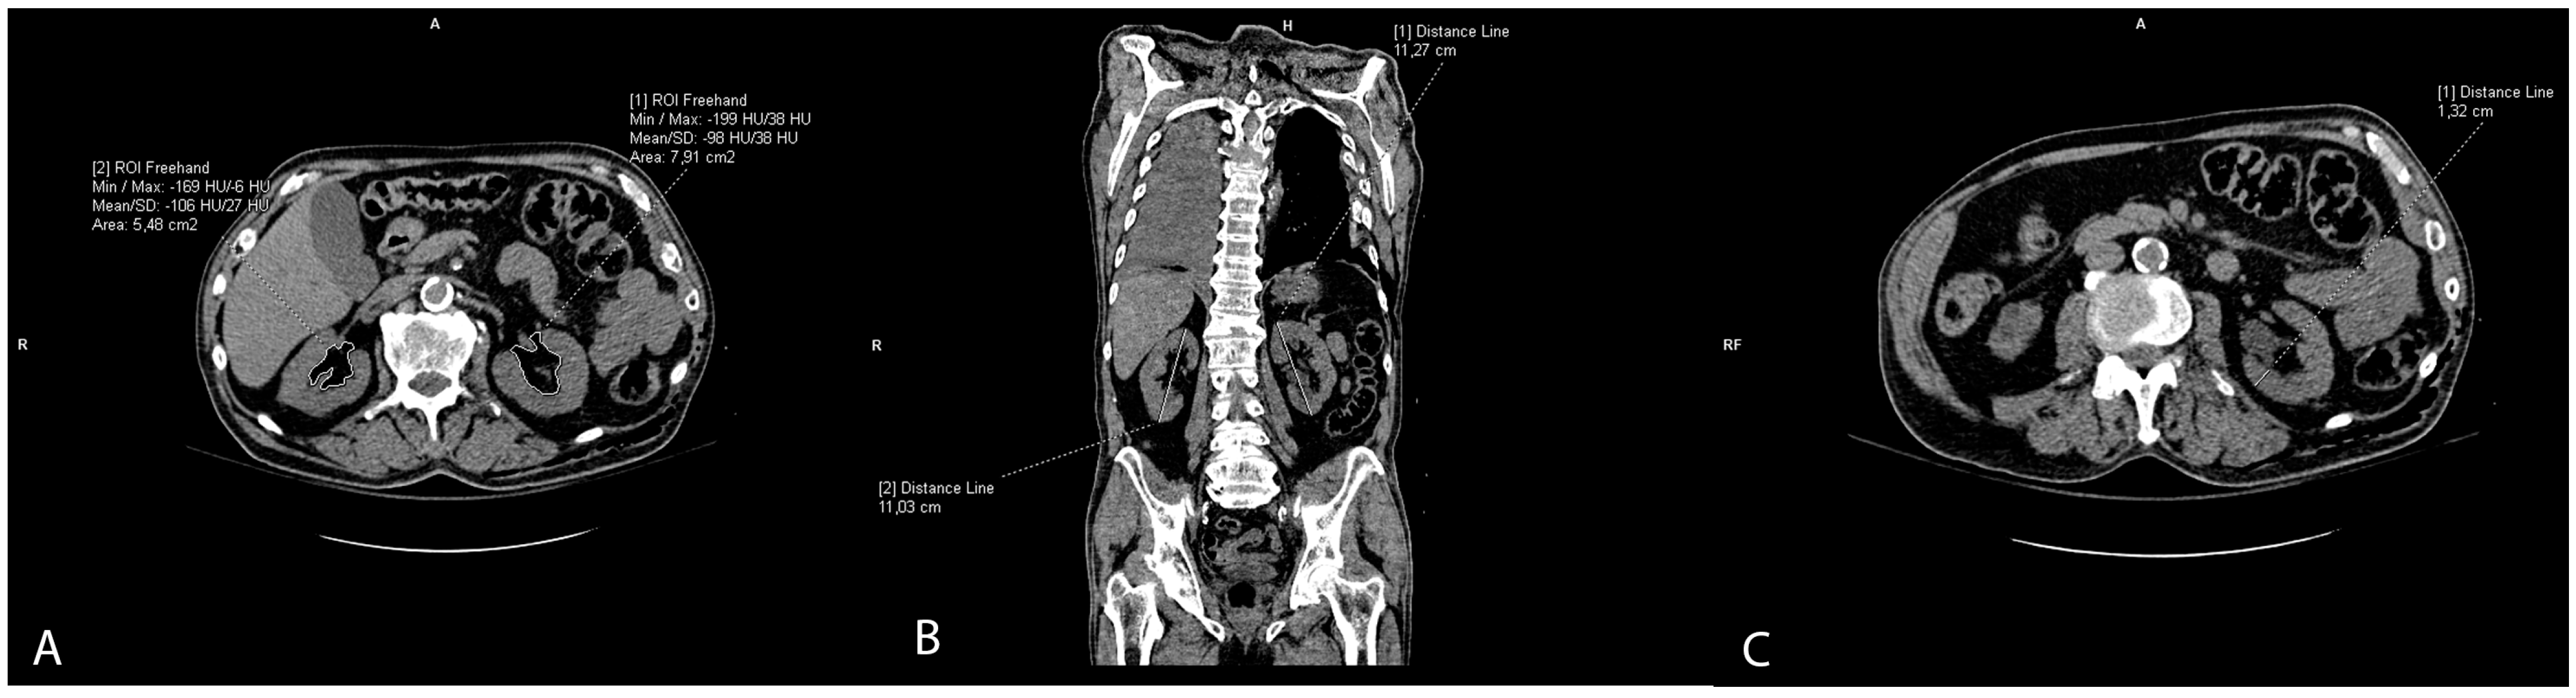

2.2. Vascular Calcification Measurement

Vascular calcifications were measured by trained radiologists using the Siemens (Munich, Germany) Syngovia post-processing tool “Ca Scoring”, which estimates calcifications on native CT scans. The tool is routinely used for coronary artery calcifications with Agatston score calculation. Each researcher passed training prior to the measurements. The procedure was as follows: on the native/pre-contrast scans, each calcification of the thoracic and abdominal aorta and both renal arteries was manually labeled (Figure 1A) and added up to the total volume of calcification of each artery. If the vascular calcifications were too close to the bone structures (spine) or were extending into an adjacent artery (for example thoracic into abdominal aorta), the freehand regions of interest (ROIs) on all scans where the lesion extended were used to delineate calcifications of interest and calculate calcification volume (Figure 1B,C). Finally, the volume of calcification within each artery was expressed in mm3 [22].

Figure 1. Representative axial CT images showing arterial calcification measurement using syngo.via postprocessing software VB60A_HF08 (A), and freehand ROI measurement of calcification volume (B,C).